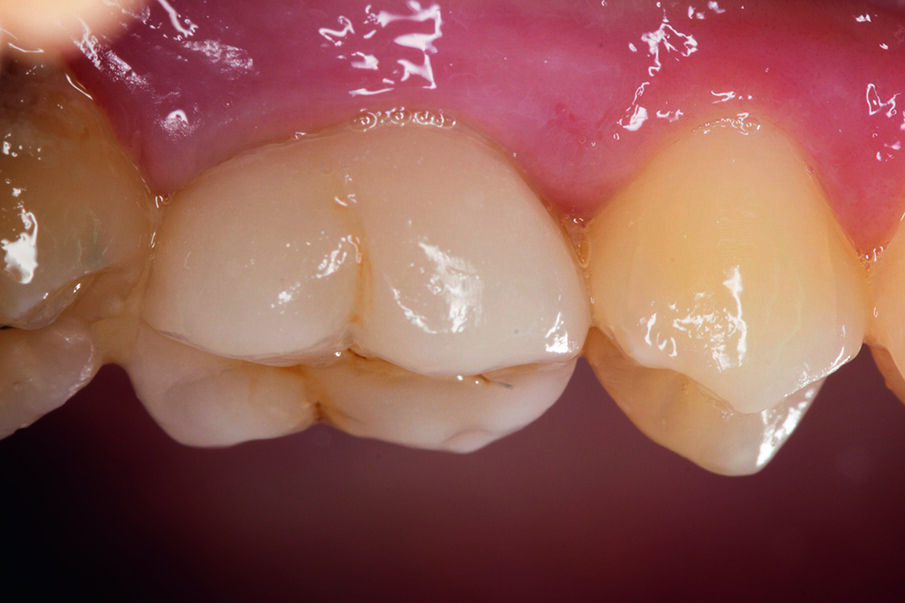

This case below shows a posterior tooth with an endodontic treatment followed by an indirect crown restoration. SDR® Plus is used as a core build up material before the crown was seated.

Fig. 6: View of the tooth – with the SDR® Plus core prepared for crown seating..